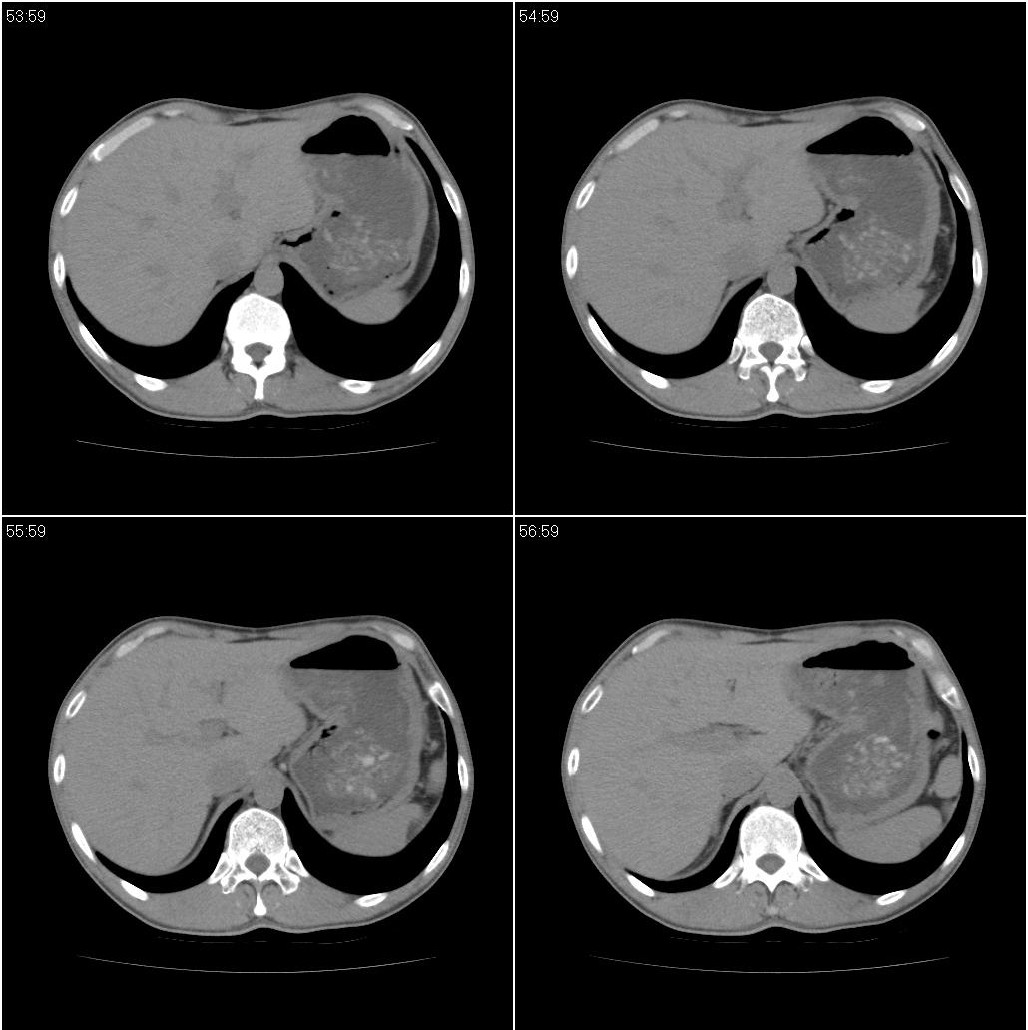

男性,47岁。近来咳痰、咳血,血沉增快(40左右),痰中未检出结核杆菌。

两肺继发性肺结核并多发性结核球形成,部分病灶内空洞形成。